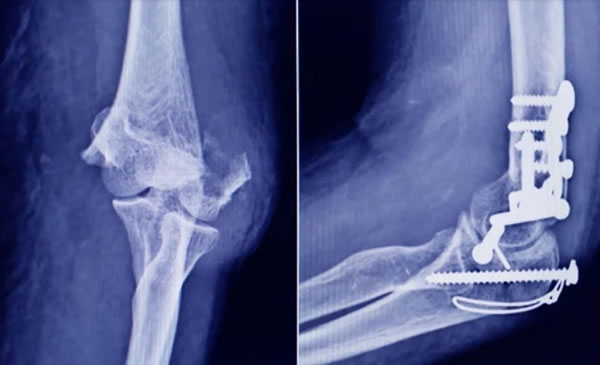

La Administración Nacional de Medicamentos, Alimentos y Tecnología Médica (ANMAT) advirtió a la población por un tornillo utilizado en cirugías traumatológicas debido a que es falso, por lo que su uso representa riesgo para la salud del paciente al que se lo implante.

Se trata de un tornillo utilizado en cirugías traumatológicas que fue detectado durante una inspección de control de mercado realizada en una ortopedia ubicada en la ciudad de San Miguel de Tucumán.

Dicho tornillo es producido por la firma Stryker Corporation, que se encuentra registrada ante ANMAT bajo el PM 594-139. Luego de la inspección, se exhibió la muestra recolectada ante la responsable técnica de dicha empresa, quien afirmó que se trataba de un producto falsificado.

Las autoridades de la ANMAT dieron a conocer las características del producto para su advertencia: STRYKER 10 mm X 28 mm – BIOABSORBABLE – ACL INTERFERENCE SCREW – REF 234-010-067 – LOT 90905.